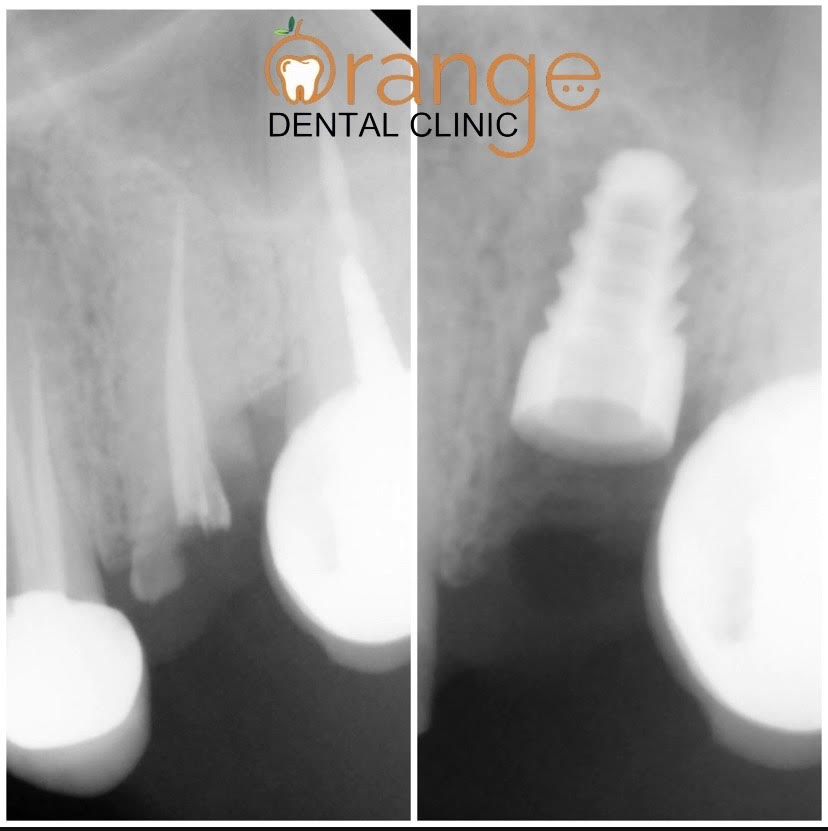

Rusults of Dental Implants